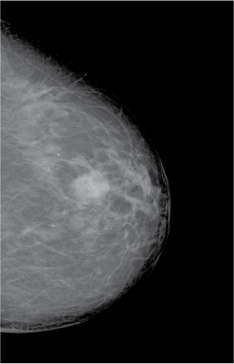

Some types of tissue – for example breast tumours, which are denser than the surrounding tissue – can also be differentiated by X-rays (Figure 2).